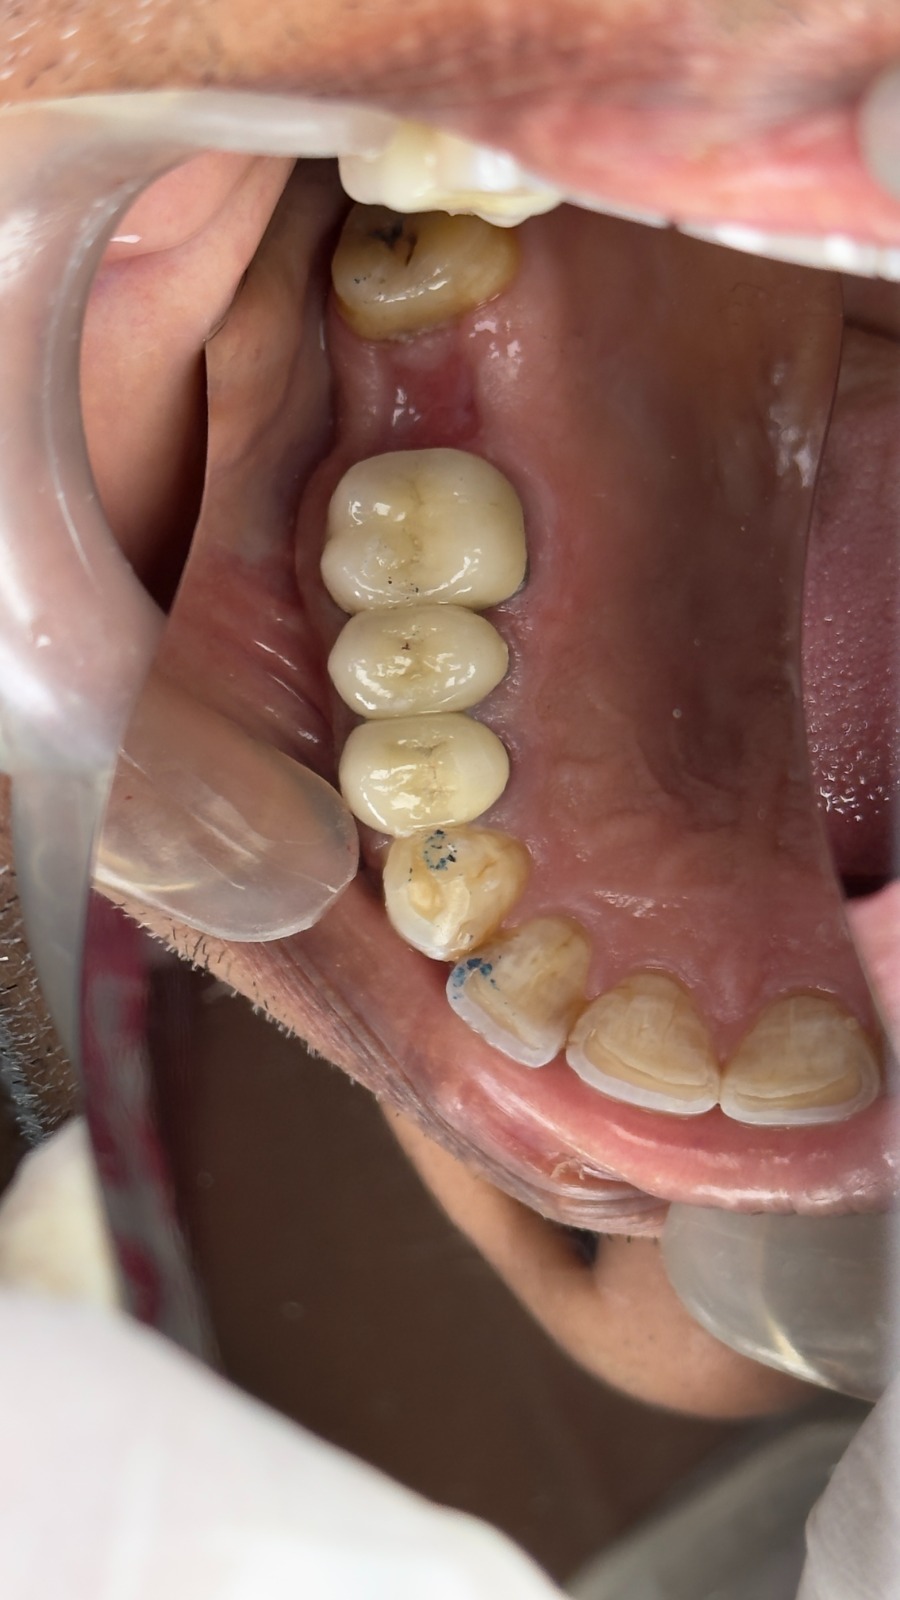

4. Final Crown Placement

The DMLS crown was cemented, ensuring that chewing forces were distributed along the natural axis of the tooth, reducing fracture risk and enhancing longevity.

After Treatment

- Fully restored tooth with strong structural support

- Stable and functional for daily chewing

- Natural appearance with improved confidence

The treatment successfully restored both function and stability of the tooth.